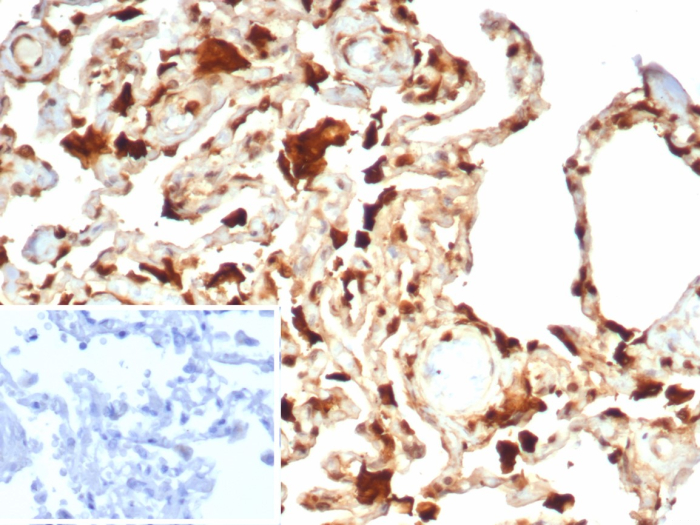

Formalin-fixed, paraffin-embedded human lung stained with S100A11 Mouse Monoclonal Antibody (S100A11/7392). Inset: PBS instead of primary antibody; secondary only negative control.